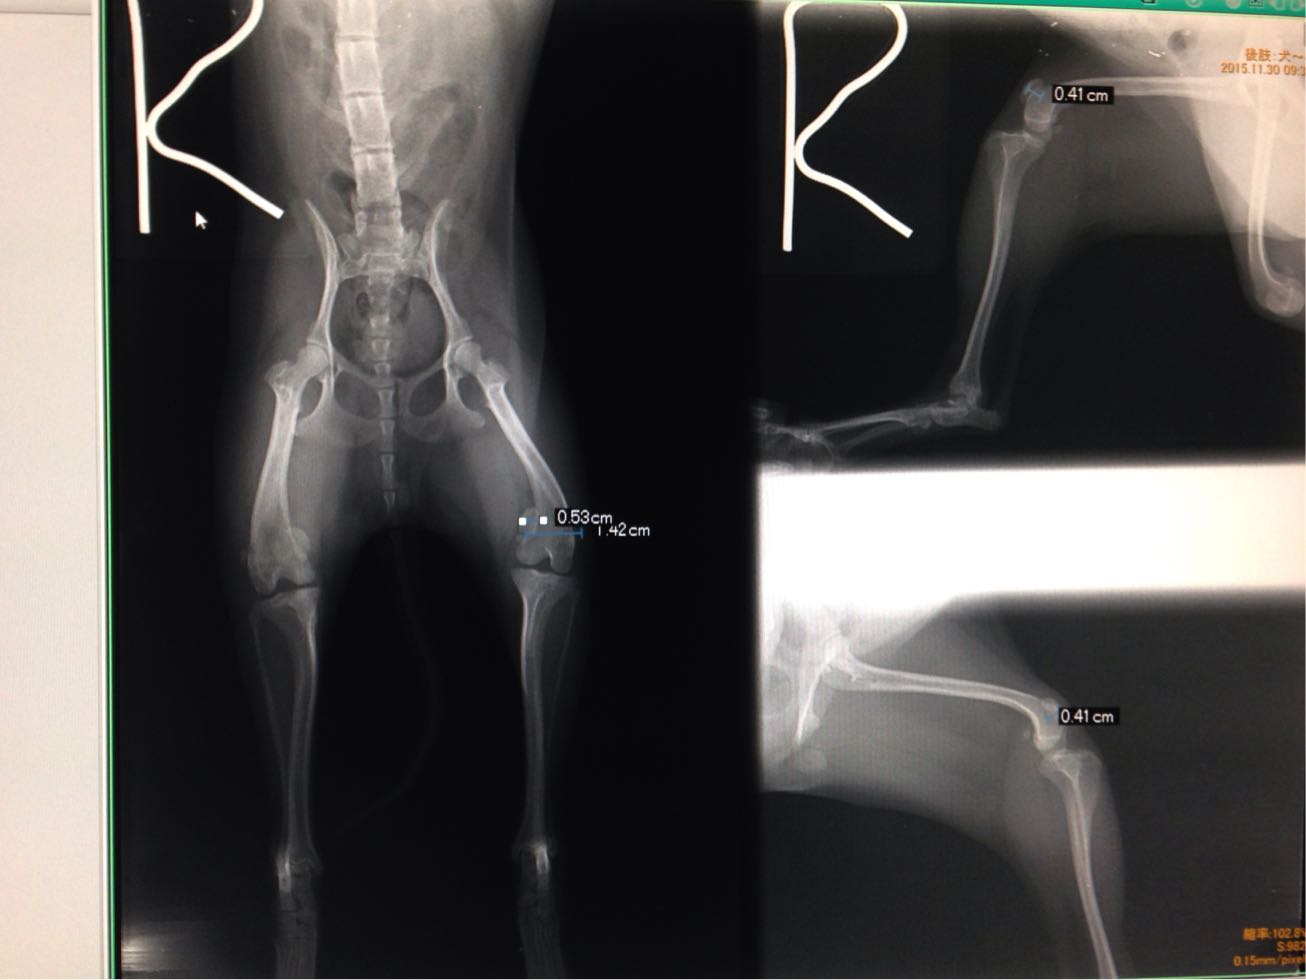

パテラ、リハビリスタート。

1月7日にパテラ手術を受けたモカちゃん、

上手くお皿が膝に乗ってくれていると良いんですが、

まだ右足が残っていますしね。